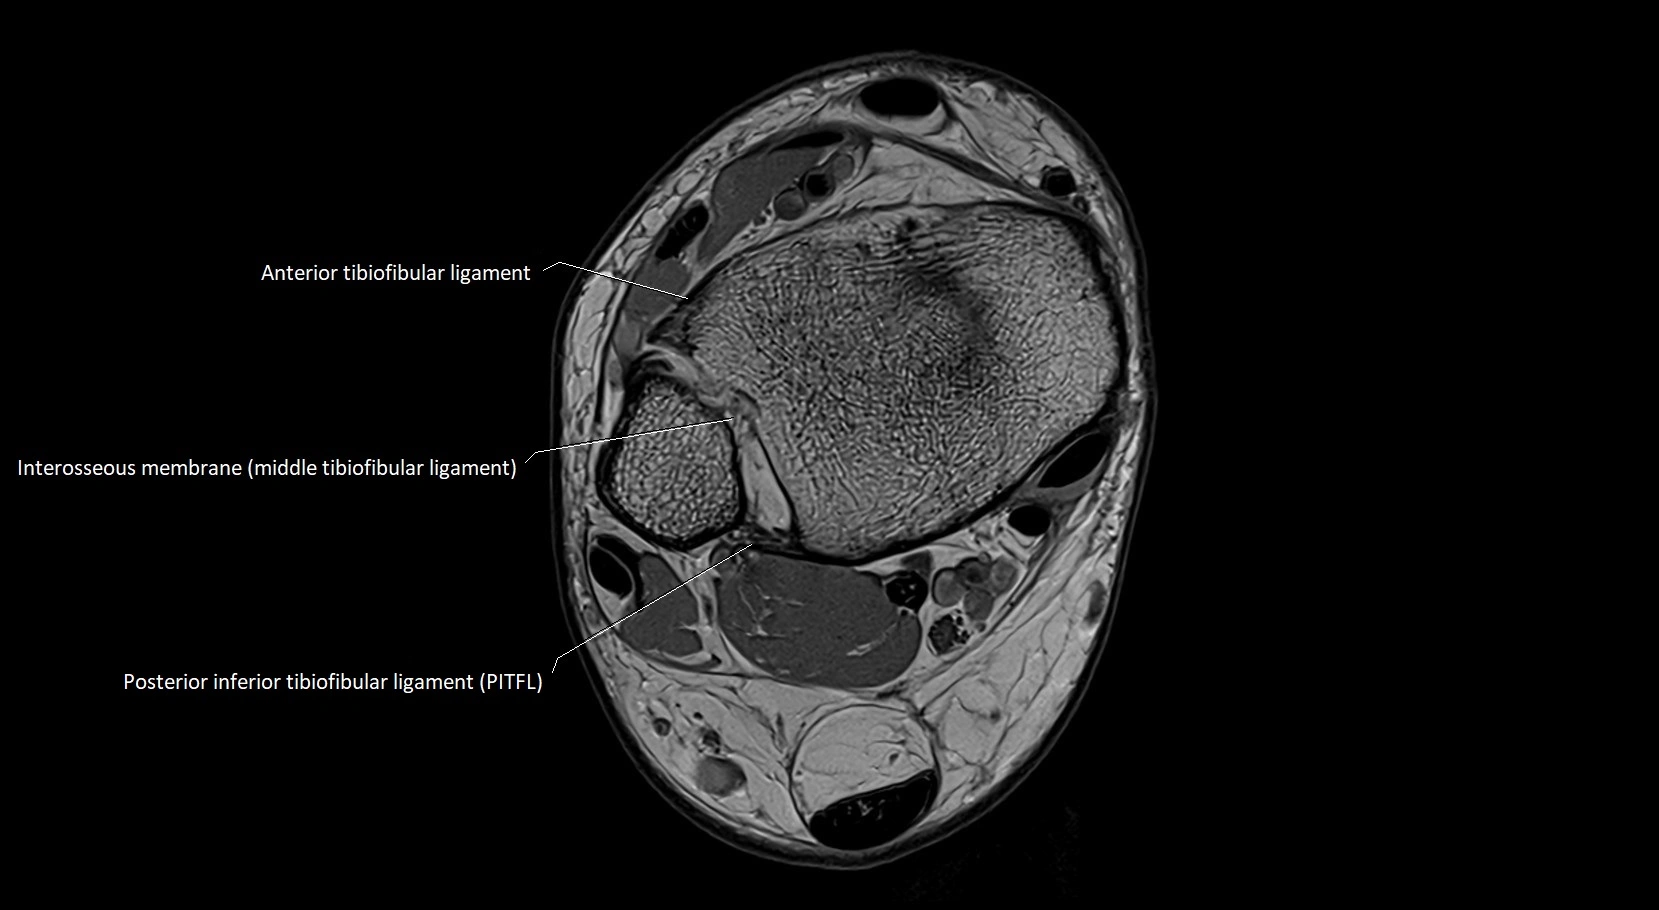

MRI image

image